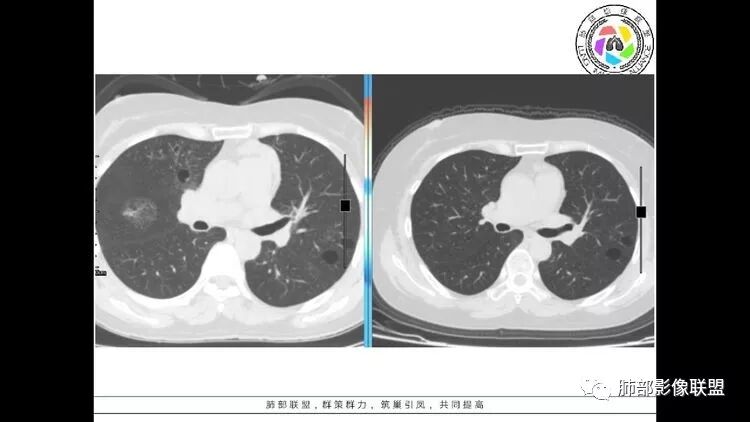

左肺下叶混杂密度病灶,其内可见空泡,周围ggo清楚,考虑浸润性腺癌。双肺散在多发薄壁囊腔和实性结节,以胸膜下及血管旁分布位于,气囊可见血管贴边征,双肺小叶间隔及中央间质增厚,局部可见磨玻璃影及树芽征,纵隔内淋巴结肿大,考虑LIP

综上,考虑左下肺浸润性腺癌+LIP

双肺多发大小不等囊腔,可见薄壁,部分囊腔内可见血管影,伴双肺多发结节,结合患者眼病及类风湿病史,考虑LIP可能大。另左肺下叶磨玻璃结节,边界清晰,内可见空泡,伴纵膈多发肿大淋巴结,不除外浸润性腺癌可能。

双肺多发囊腔伴结节 部分结节周围有晕 边缘清 前纵隔多发淋巴结增大 考虑lip伴淋巴瘤?

常规分析:右眼红疼1天,滴眼史两年,有类风湿病史,考虑有干燥综合征(SS)可能,需要了解自免抗体检测情况,双肺囊变需要考虑LIP,另右上叶前段GGO要鉴别腺癌或转移可能,右下叶背段多发树芽改变,双肺多发实性小结节,结核?左下肺混合性GGO考虑侵润性腺癌可能,双侧胸膜下多发结节,部分合并GGO改变,右侧腋窝及纵隔淋巴结多见,转移?最后问题来了,这个病人一元(腺癌合并转移,包括整个囊变,实性结节,胸膜下都是转移)?二元(LIP合并腺癌伴转移或者淀粉样变基础上的LIP)?三元(LIP+结核+腺癌伴转移)?